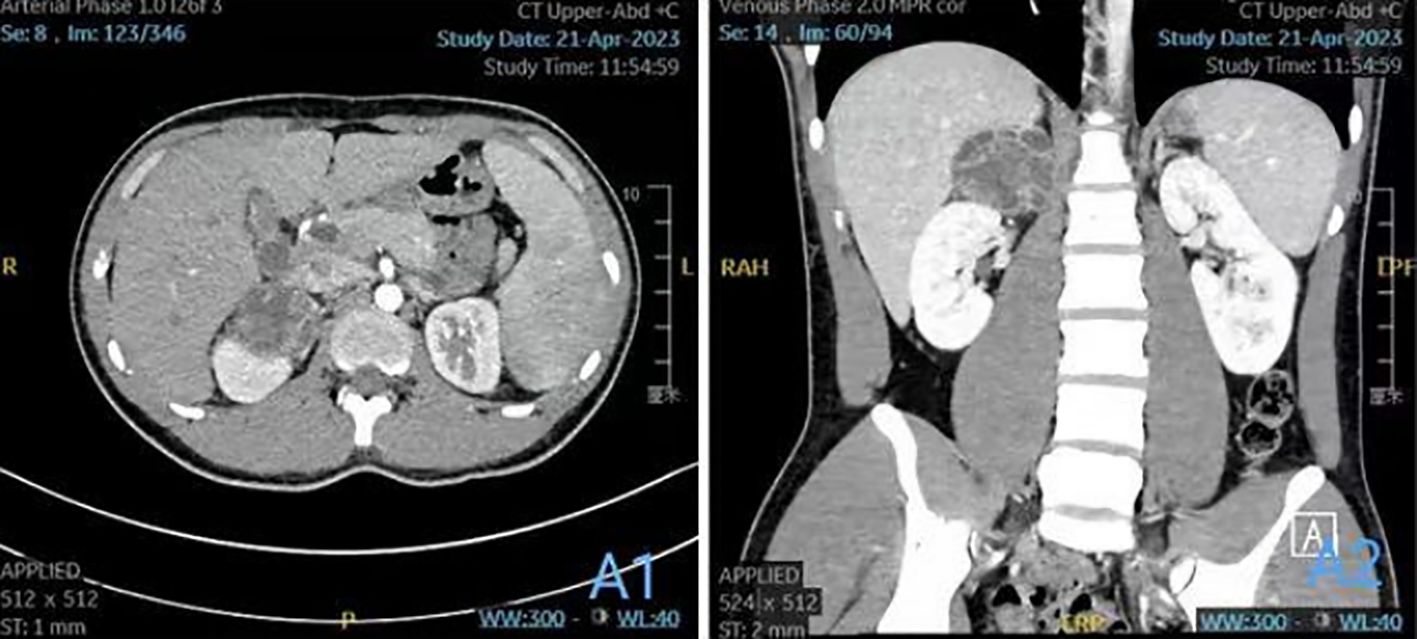

Preoperative computed tomography angiography and urography (CTA+CTU) revealed a well-circumscribed, low-density mass (approximately 5.7×5.1×4.5 cm) in the right adrenal gland. The solid components showed enhancement on contrast administration (Figures 1A1, A2). The enhancement pattern was heterogeneous, with areas of avid contrast uptake in the arterial phase and washout in the delayed phase, features that can be associated with both hypervascular tumors like pheochromocytoma and certain soft tissue sarcomas. The liver, gallbladder, spleen, pancreas, and kidneys appeared normal in size, shape, and attenuation, with no abnormal enhancement. The abdominal bowel was normally distributed without dilation or effusion. No definite masses, enlarged lymph nodes (hepatic hilum or para-aortic), or peritoneal effusion were observed. The initial differential diagnosis included a left adrenal solid-cystic mass, with considerations of pheochromocytoma or ganglioneuroma.